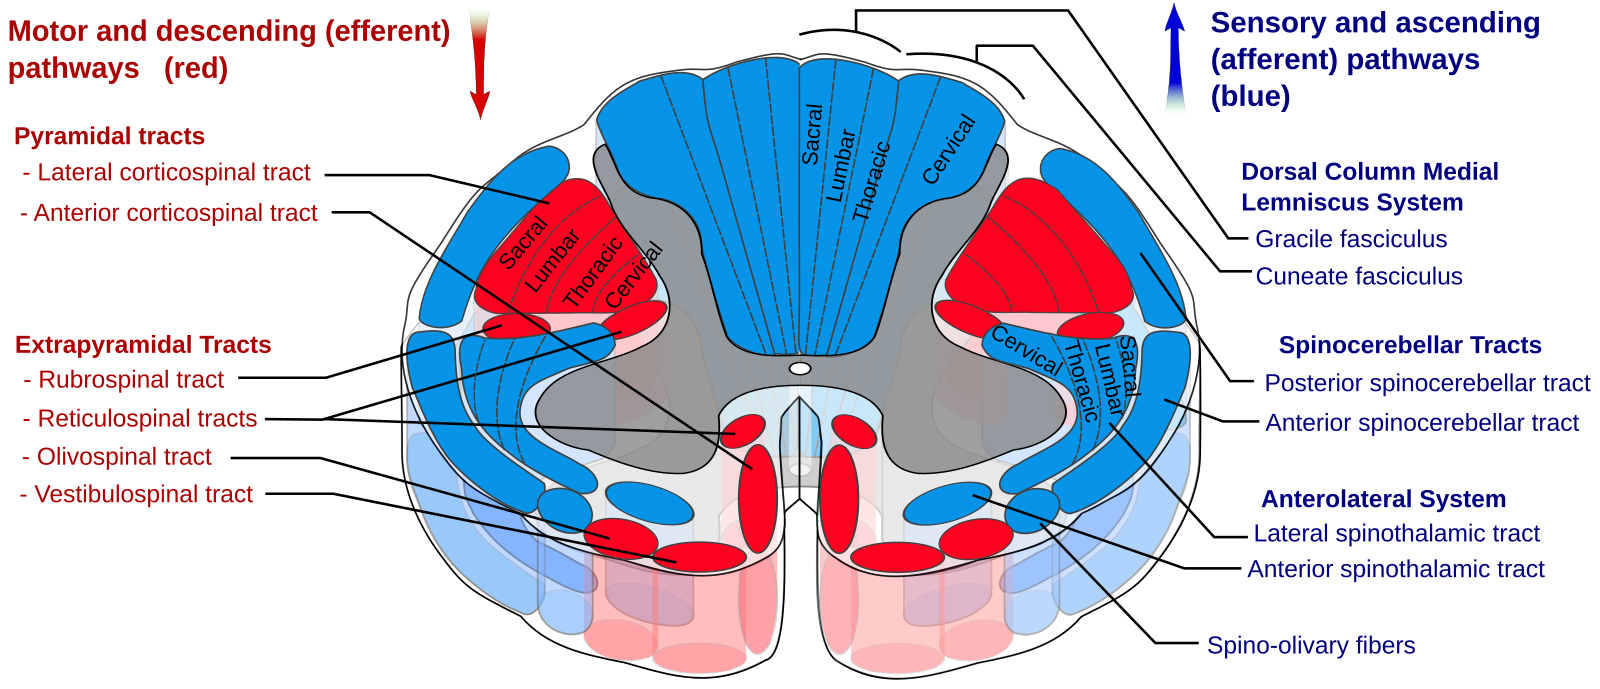

Illustration of the motor neuron tract descending from primary motor cortex, via spinal cord, to skeletal muscle. - Extrapyrimidal Tracts

Descending pathways in mammals.

A labelled cross-sectional diagram of the tracts of nervous pathways in the human spinal cord. - UMN or LMN damage causing flaccid paralysis